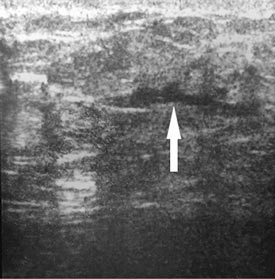

Наглядно ультразвуковая картина послеоперационных ран представлена на рис. 1–5. Показана положительная динамика разрешения полостных образований послеоперационной раны на 3-и, 5-е и 7-е сутки. Переход гипоэхогенной зоны в сторону уменьшения и появления участков гиперэхогенной структуры на 7-е сутки послеоперационного периода свидетельствует об уменьшении воспалительных процессов, снижении риска увеличения полостных образований и формировании фазы регенерации.

Рис. 5. Ультразвуковая картина передней брюшной стенки живота того же больного (см. рис. 3, 4) на 7-е сутки после лапаротомии. Гипоэхогенная зона в области белой линии живота отсутствует. Определяются гиперэхогенные участки

На 5-е сутки послеоперационного периода в определённых участках раны мышечно-апоневротического слоя появились признаки гиперэхогенности тканей, что свидетельствовало о переходе в фазу регенерации и формировании соединительнотканного рубца. Данные подтверждаются клиническими признаками заживления. На основании литературных источников можно заключить, что к 5–7-м суткам послеоперационного периода в области лапаротомной раны завершаются экссудативные процессы, прекращается выделение секрета из раны, наступает фаза регенерации [17].